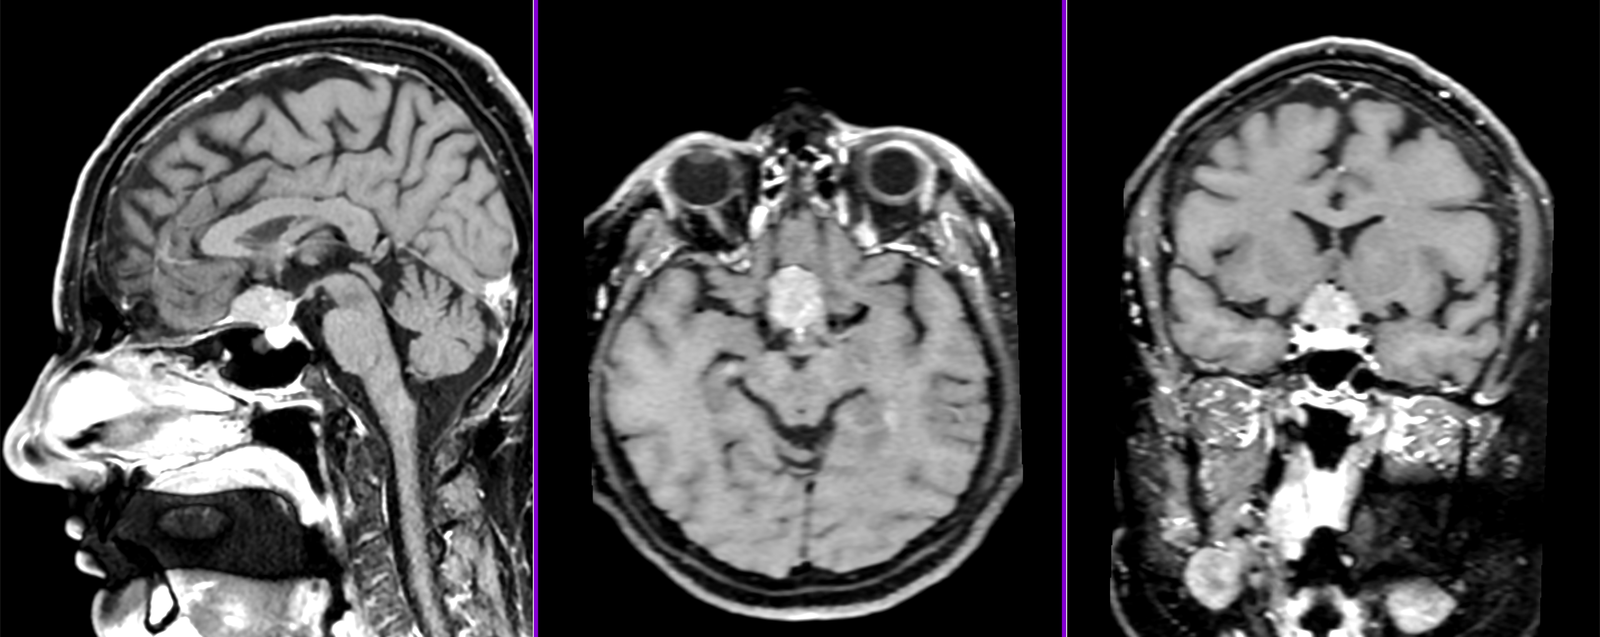

Meningiom olfactiv – RMN preoperator

Meningiom olfactiv – RMN postoperator

- RMN – cea mai completă investigație, oferă detalii despre relația cu țesutul cerebral, vasele de sânge și nervii Captarea substanței de contrast este deosebit de importantă.